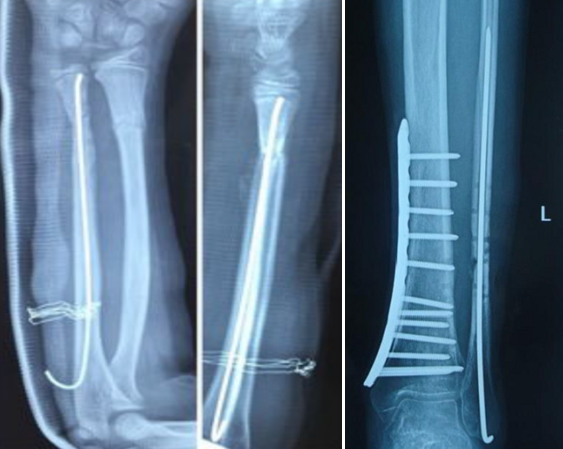

8、克氏针长期固定

使用克氏针代替弹性髓内钉治疗小儿以及成人骨折,同样可以取得非常好的治疗效果。